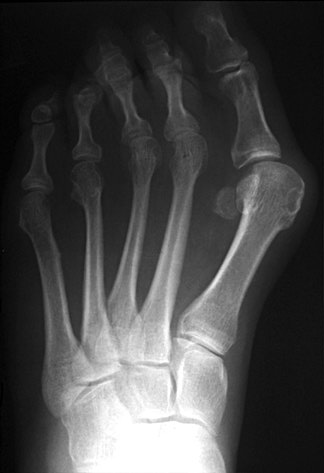

BilatHV:

This patient has a marked hallux valgus deformity in both feet. As the first toe migrates more and more to valgus, it presses against the second toe, and may aggravate dorsal clawing of the second toe, which is usually initiated by overload of the second metatarsal and synovitis of the metatarsophalangeal joint. Also note the relative hyperostosis of the second metatarsal shafts compared to the third and fourth, as well as dorsal rotation of the fibular sesamoids.